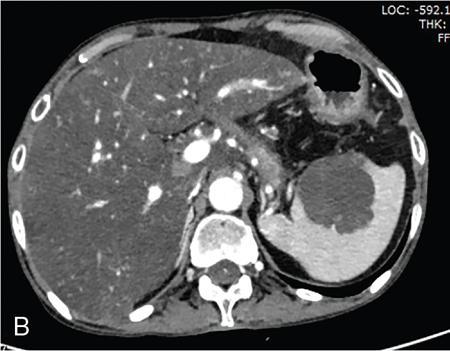

Vijay Kumar K.R. CONGENITAL SPLENIC ABNORMALITIES A multitude of variants and pathologies affect the spleen and it is pertinent for a radiologist to be aware of the common imaging appearances of the same. The spleen begins to develop in the fifth week of gestation from a mass of mesenchymal cells that condense between the two leaves of the dorsal mesogastrium. Several such aggregates fuse to form the lobulated embryonic spleen. The spleen is translocated to the upper left side of the abdominal cavity due to rotation of the stomach and differential growth of the dorsal mesogastrium. The mesogastrium fuses with the peritoneum over the left kidney and forms the splenorenal ligament. The lienorenal ligament fuses dorsally and the splenic artery courses behind the peritoneum as it enters the splenorenal ligament. The portion of dorsal mesentery between the stomach and spleen forms gastrosplenic ligament. Differentiated mesenchymal cells form the parenchyma, connective tissue and capsule of the spleen. The foetal spleen shows lobulations, which normally disappear before birth. However, they may persist along the medial part of the spleen. Sometimes a persisting portion of the spleen may extend medially and anteriorly over the upper pole of the left kidney. It may be mistaken for a space-occupying lesion arising from the kidney. Rarely it may extend posterior to the upper pole of the left kidney, displacing it anteriorly (Fig. 9.22.1.1). The notches and clefts along the superior borders are vestiges of the grooves that initially separated the foetal lobules. They may be 2–3 cm deep. They may mimic a splenic laceration in a patient with abdominal trauma, and the embedded peritoneum at the waist may simulate splenic infarction or haematoma. Hence caution should be exercised. A normal spleen which does not have a fixed ligamentous attachment can change position within the abdomen and is hence known as a wandering spleen. The spleen is normally anchored by the gastrosplenic and lienorenal ligament. Absence or weakness of one or more ligaments that affix the spleen. The spleen with its vascular pedicle as the sole attachment can become a hypermobile intraperitoneal organ. Rarely, the spleen may be normal in position with a wandering accessory spleen. Pregnancy (due to hormonal effects), prune belly syndrome, splenic cysts, malaria, Hodgkin’s disease and lymphangioma. Some of the affected patients may be asymptomatic and diagnosis may be incidental. Clinically it presents as a mobile, palpable, notched mass. Pressure on the vascular pedicle or torsion causes symptoms such as acute abdominal pain, nausea and vomiting. Torsion involving the tail of the pancreas may present as pancreatitis. Confirms the absence of spleen in the left upper quadrant of abdomen with identification of splenic tissue at an ectopic site. Power Doppler, colour Doppler and duplex sonography allow for the identification of blood flow in the splenic vessels and parenchyma. Intermittent torsion may be responsible for an enlarged spleen. Pathognomonic feature of wandering spleen is absence of the spleen in the upper abdominal cavity and presence of a well-demarcated, homogeneously enhancing mass of soft tissue in the pelvis or abdomen. Sometimes a wandering accessory spleen can be visualized as a long vascular pedicle connecting a small mass to the splenic vessels (‘jokari sign’). It can locate ectopic splenic tissue and can also indicate the viability of the tissue. Splenic vessel anatomy can be well demonstrated. 99mTc-sulphur colloid scintigraphy and heat denatured 99mTc-labelled red blood cell imaging provide useful information regarding size and location of splenic tissue. Torsion is indicated by lack of tracer activity in a previously demonstrated wandering spleen. Twisting and torsion of splenic artery can be demonstrated by celiac arteriography. The venous phase may demonstrate splenic vein obstruction with collateral circulation and varices. A congenital focus of normal splenic tissue that is separate from the main body of the spleen is known as an accessory spleen. It results from the failure of fusion of some embryonic splenic buds within the dorsal mesogastrium. Its incidence varies from 10% to 30% on autopsy examinations. They vary from a few millimetres to several centimetres in diameter. They most commonly are found around the splenic hilum. The second most common location is the pancreatic tail. They can also be found in the stomach wall, omentum, mesentery, large bowel and scrotum. Reveals a round or oval mass of tissue around the splenic hilum that is isoechoic with the main spleen. On noncontrast images they are isodense to the main spleen. CECT reveals serpiginous enhancement on arterial phase followed by homogeneous enhancement on venous phase-like spleen (Fig. 9.22.1.2). Accessory spleen is mildly hypointense to the spleen on T1 images and isointense on T2 images. Contrast administration reveals enhancement similar to that of spleen on the arterial, portal and late phases. It is isointense to spleen on DWI images with similar ADC values. 99mTc-sulphur colloid scintigraphy and heat denatured 99mTc-labelled red blood cell imaging show functional uptake in splenic tissue and differentiate splenule from other masses. PET CT-FDG avid mass can mimic tumour. Surgical resection is the preferred mode of treatment in the background of hypersplenism or lymphoma. It is characterized by an ectopic splenic tissue or an abnormal connection between the gonad and the spleen. The left side is more commonly involved than the right side. The accepted theory is that splenic gonadal fusion occurs due to abnormal attachment of the splenic anlage in the left dorsal mesogastrium with the left urogenital fold, during the fifth to eighth weeks of gestation. It has a higher male preponderance and can interfere with left testicular descent and closure of processus vaginalis. It commonly presents as inguinal hernia and cryptorchidism. The spleen and gonad are attached by a fibrous or splenic cord across the peritoneal cavity. It is associated with limb defect syndrome, cleft palate, micrognathia, anal anomalies, craniosynostosis, spina bifida, cardiac malformations, thoracic malformations and diaphragmatic hernias. This is not associated with congenital anomalies. Shows a well-defined scrotal mass with echotexture similar to that of spleen. Confirms splenic tissue in inguinal or scrotal area. It is characterized by the absence of spleen with duplication of right-sided structures. (Right isomerism). It has a slight male preponderance with an incidence of 1 in 40,000 live births. It has a poor prognosis due to its high association with congenital cardiac abnormalities (Fig. 9.22.1.3). It is of uncertain aetiology, and maybe associated with the mutations of CFC1 gene, SHROOM3 gene etc. Delayed development of embryonic curvature can be another cause. It is also theorized that it can be caused due to vascular compromise by pressure on splenic blood supply from adjacent structures. Splenectomy – Usually has a surgical history and is not accompanied by associated anomalies. It is a heterotaxy syndrome associated with multiple spleens and duplication of left-sided structures. (Left isomerism). It has an equal gender predilection with a slightly higher female preponderance. It has a fairly better prognosis than asplenia and is associated with a lesser incidence of cardiovascular anomalies (Fig. 9.22.1.4). It is of uncertain aetiology, and maybe associated with the mutations of CFC1 gene, SHROOM3 gene etc. Accelerated development of embryonic curvature can be another cause. SPLENIC INFECTION AND ABSCESS The infection of the spleen can show three patterns. Fungal and granulomatous infections usually present with multiple micronodules. A pyogenic abscess usually manifest as a solitary lesion. Imaging of diseases causing splenic nodules is never the sole basis for diagnosis. The clinical presentation and laboratory testing (tumour markers, tuberculosis testing and bone marrow biopsy) help in establishing an accurate diagnosis. The imaging findings are nonspecific and the nodules may vary in size from a few millimetres up to 2 cm in diameter. They maybe hypoechoic on ultrasound and hypoattenuating on CT. They are of low signal intensity on T1-weighted sequences and vary from hypointense to hyperintense on the T2-weighted sequences. The nodules show no enhancement or show ring enhancement after contrast study. Healed granulomas are seen as scattered, discrete, small calcifications in an otherwise normal spleen. With increasing number of immunocompromised patients, such as oncology patients undergoing aggressive chemotherapy, critically ill patients in intensive care units, injection drug abusers, and HIV-infected patients, there is rise in the incidence of splenic abscess. For splenic abscess to develop, it may require the presence of bacteremia (sepsis and septic emboli) and altered splenic architecture, which is caused secondary to a haematoma, infarct, or sickle cell disease. Abscesses can also develop from the extension of infection from adjacent organs, like in cases of infected pancreatitis and perinephric abscess, which are less common. In about 20% of cases, cause or source could not be discovered. Abscesses can be unilocular or multilocular, solitary or multiple, depending on the causative organisms and patient’s immunity. Mortality ranges from 15% in otherwise healthy patients with unilocular splenic abscess to 80% in immunocompromised patients with multiple abscesses. Abscesses which are multilocular, gas-containing or due to gram-negative bacillus show poor prognosis. A pyogenic abscess is usually solitary, unilocular/multilocular, but it can also be multifocal. These are uncommon and are reported in 0.14%–0.70% of large autopsy series. Most common presentation is fever (92%), left upper abdominal pain (77%) and leucocytosis (66%). Other symptoms are left pleural effusion and splenomegaly. It can be solitary or multiple, unilocular or multilocular. The appearance of splenic abscess depends on the stage of development. In the early stages of the disease, an abscess appears as an ill-defined mass later developing into a complex collection with septations, debris and sometimes gas. In later stages, after a capsule is developed, the lesion becomes well defined. Left pleural effusion is seen in around 42% of cases. Left lung base atelectasis in 20% of cases and splenomegaly is seen. Abscess with air can be identified based on the presence of extraluminal gas or air–fluid levels in the left upper quadrant. Ultrasonography has a sensitivity of 75%–98% in detecting splenic abscess. This is a very useful modality in patients who are bedridden, with renal impairment and for assessment of small splenic lesions (Fig. 9.22.2.1). Ill-defined hypoechoic mass mimicking a mass is seen in the early phase of the infection and a complex mass with internal septations, debris, rarely acoustic shadowing caused by gas is seen in later stages. The capsule appears as a thin hyperechoic rim. It is noninvasive, speedy, and a modality with high sensitivity (92%–98%). It helps in differentiating unilocular from multilocular lesions and, gives exact anatomical localization and information about perisplenic area, which later helps in planning-guided management procedures. An abscess is seen as a hypodense collection or complex cystic lesion with enhancing rim on the postcontrast study (Fig. 9.22.2.2). CT may help in identifying concurrent areas of infection and, thus, the source of infection. On CT, an abscess may look similar to an infarct, haematoma, or neoplasm. An infarct lacks mass effect, unlike abscess or tumour (Fig. 9.22.2.3). The presence of gas within the lesion is diagnostic of abscess; however, this finding is rare. Splenic abscesses show low signal on T1-weighted images and high signal on T2-weighted images compared with the normal spleen. Minimal to intense peripheral enhancement is seen after IV administration of gadolinium. But MRI is not routinely done, as many patients are clinically unstable. This plays a limited role in the detection and localization of splenic abscess. A nonspecific filling defect is seen on a 99mTc-sulphur colloid scan within spleen if the size is more than 2 cm in diameter. Normal inherent splenic activity on 67Ga scans and 111In-labelled leukocytes scans obscures any kind of inflammatory focus in the spleen, giving rise to false-negative examination. 67Ga scans are nonspecific as tracer uptake can be seen in neoplastic conditions such as lymphoma. Detection and characterization of the abscess are better done if 99mTc-sulphur colloid scan is done prior to 111In-labelled leukocytes scan. FDG PET/CT can also detect the site of infection but not used in the diagnosis of splenic abscess. Early diagnosis of an abscess is prompted for a better outcome. Based on laboratory findings, appropriate antibiotic therapy initiated. USG or CT-guided percutaneous aspiration is tried if the abscess is less than 5 cm in size, and for larger abscesses, percutaneous drainage procedures are done preserving the spleen. Splenectomy is reserved for complicated infections. Fungal abscesses are usually seen in immunocompromised patients with neutropenia such as patients with acquired immunodeficiency syndrome (AIDS), on chemotherapy and immune suppressive agents, and with lymphoproliferative disorders. With the advent of aggressive chemotherapy, the incidence of splenic fungal infections has increased. Approximately 7% of patients with acute leukaemia have hepatosplenic fungal infections. Multiple microabscesses are common. Hepatosplenic candidiasis lesions are very small, and before the advent of CT and MRI, their detection was too difficult. They measure in the range of 5–10 mm in diameter; however, they may be even miliary (<5 mm). Infections are mostly caused by candida species. Other organisms are aspergillus, Histoplasma and Cryptococcus. Imaging characteristics depend on the stage and severity of neutropenia. In cases of chronic disseminated infections with poor neutrophil counts, sometimes lesions are not visible as the host fails to produce an immune response. Lesions become apparent once neutrophil counts improve. Patients presenting with fever and splenomegaly are not improving on conventional antibiotic therapy, and with associated immunocompromised status, fungal infections are to be considered. No single imaging is specific or sensitive in establishing the diagnosis. Serial imaging is needed to detect hepatosplenic involvement; however, tissue diagnosis is the gold standard. Four different patterns are seen in hepatic candidiasis. Multiple, small, homogeneous hypoechoic nodules are the most common finding. Less commonly wheel-within-a-wheel appearance (i.e. the target sign) is seen in the early stage of infection. The first wheel is the peripheral hypoechoic zone of fibrosis and an echogenic second wheel of inflammatory cells around a central hypoechoic nidus containing necrosis and fungal elements. Later these lesions evolve into Bull’s eye lesion where there is a central echogenic focus surrounded by a hypoechoic halo. Lesions become small and hyperechoic with various degrees of posterior acoustic shadowing, with or without calcification, or they may even disappear later in the course of the infection. Splenic nodules are hypodense lesions measuring in the range of 5–10 mm. Only 30% of cases are detected in noncontrast studies. They often have low attenuation, although there can be a focus of high attenuation or a ‘wheel-within-a-wheel’ pattern. Peripheral ring of enhancement is noted in around 70% of cases in the arterial phase of CT, and it is said to disappear on the portal venous phase. There is no significant difference in the detection of the lesions between arterial and portal venous phases of contrast studies. MRI is said to be the investigation of choice for diagnosis of hepatosplenic candidiasis and is superior to CT and USG, especially when short-time inversion recovery sequence is used. MR imaging is also used to monitor the response to antifungal therapy. Based on MRI findings different phases of hepatosplenic candidiasis are described. Lesions are small, measuring less than 1 cm in diameter. They show mildly hypointense on the T1-weighted images and markedly hyperintense on the T2-weighted images. In 2 weeks to 3 months, acute lesions are transformed into subacute lesions. The lesions reveal mildly increased signal on both T1- and T2-weighted sequences. On all sequences, a peripheral ring of very low signal intensity is seen. Following the gadolinium administration, the central region of the lesions show enhancement; however, the peripheral ring continues to have low signal intensity, making them more obvious. It takes from 3 months to more than 1 year for the healed fungal foci composed of fibrous tissue of differing densities and degrees of vascularization to appear on MRI. The lesions measure 1–3 cm, become irregular, and the central area disappears. Chronic healed fungal abscesses have low signal intensity on T1-weighted images and are isointense to mildly hyperintense on T2-weighted images. No perilesional dark ring is noted. These lesions are moderately hypointense on early postgadolinium images and minimally hypointense on delayed postgadolinium images. Mycobacterial tuberculosis infections are mainly seen in immunocompromised patients. Spleen involvement is seen in disseminated, miliary infection in about 80%–100% of autopsy cases; however, it is documented less on imaging. Splenic tuberculosis is seen in the form of nodules measuring ∼ 0.2 and 1 cm in diameter. The macronodular form is very rare (Fig. 9.22.2.4). Hypoechoic pattern is seen. Hypoattenuating nodules with lymphadenopathy noted. Depending on the different stages of the tubercular process, intensities on T1- and T2-weighted images vary. On contrast-enhanced T1-weighted images, lesions most often show peripheral enhancement less commonly gradual peripheral enhancement with complete filling is noted. It is also called as Mycobacterium intracellulare infections. These are also typically seen in immunocompromised patients. Splenomegaly with multiple, low attenuation nodules is seen. Associated findings such as hepatosplenomegaly, diffuse jejunal wall thickening and enlarged lymph nodes are seen. Lymph nodal involvement is homogeneous as opposed to Mycobacterium tuberculosis infections. Focal splenic or hepatic lesions are noted in about 30% of patients with HIV who are infected with M. tuberculosis but are rarely noted in those infected with M. avium intracellulare. Marked splenomegaly is more common in M. avium intracellulare than in M. tuberculosis infection. It is a common opportunistic infection in patients with HIV. Extra pulmonary involvement manifested in the form of necrotizing granulomas. Spleen involvement is an incidental finding. When treated the nodules may enlarge and become progressively calcified in a rim like or punctate fashion. Disseminated infection can show punctate calcification in adrenal glands, pleural or peritoneal effusions, that subsequently calcify. Splenomegaly with small hypoechoic lesions with cystic components or tiny, highly reflective, nonshadowing foci or calcified granulomas. The nodules are hypodense. Calcified granulomas are seen in later stages. This is a self-limited disease caused by bartonellae henselae. Hepatosplenic involvement is rare. This disease is to be considered when a patient presents with abdominal pain, fever of unknown origin, and multiple hypodense lesions in the liver and spleen. It is also called as echinococcosis, a disease seen in endemic regions and in patients emigrated from endemic areas. The causative organism is a zoonotic tapeworm echinococcus granulosus. The most commonly involved organs are the liver, lung, peritoneum, kidney, brain, mediastinum and heart. Spleen is rarely primarily involved. Spleen is involved in approximately 2% of cases of abdominal hydatidosis. Spleen involvement is seen in case of an extensive abdominal hydatidosis, like after the rupture of liver hydatid cyst or in cases of systemic dissemination of infection. Larvae of the tapeworm incite an inflammatory response after its entry into the target tissue in the host where it forms a hydatid cysts consisting of three layers. Peri cyst is an outer layer of modified host cells forming a dense and fibrous layer. The middle layer laminated layer and an inner germinal layer made up of daughter cysts, also called as brood capsules. Scolices develop in the brood capsules. The laminated and germinal layer forms the true cyst wall. After the parasites die, the cysts become inactive, may calcify, and undergo fibrosis. Patients present with abdominal pain, splenomegaly and fever. The diagnosis is to be suspected in all patients from endemic areas presenting with a splenic cyst. A World Health Organization Working Group on echinococcosis has a standardized sonographic classification of echinococcal cysts (Table 9.22.2.1). CE, cysticechinococcosis; CL, undifferentiated simple cystic lesions. Radiological appearances depend on the natural aging process of the cyst. Classic imaging characteristics are lost when the cyst becomes secondarily infected. A ring-like or curvilinear calcification noted in the left hypochondriac region. This may represent the calcification of pericyst in later stages of the disease. Ultrasound is an easy and most commonly used for evaluation of a suspected case of abdominal echinococcal disease. It is used for the diagnosis, planning the management and follow-up. Shifting of brood capsules within the cyst causes fine internal echoes, that is ‘The snowflake sign’ (hydatid sand). Detached laminated endocysts may be seen within the cysts, that is ‘The. Waterlily sign’. Mother cysts may be partially /completely filled by daughter cysts. Calcifications with posterior acoustic shadowing are seen in later stages of the disease. CT and MRI are indicated for widespread disease and complications and for planning percutaneous therapy and surgery. Complications of a hydatid cyst include compression of the adjacent structures, cyst rupture, secondary infections, anaphylaxis and fistulization to surrounding structures. A hydatid cyst may be seen as a well-defined, hypoattenuating cystic lesion with fluid-attenuation values and a distinguishable wall. CT is more sensitive for subtle wall calcification. May appear hyperdense because of debris, hydatid sand and inflammatory cells (Fig. 9.22.2.5). In CE 2 cysts, peripherally arranged daughter cysts, completely fill them other cyst. The daughter cysts show lower attenuation than the mother cyst. Type CE 3 lesions are round or oval with occasional calcification and daughter cysts. They usually show high attenuation. Type CE 4 cysts are complex masses. Intravenous contrast administration reveals enhancement of septa and cyst wall. Type CE 5 cysts are complex cystic or solid-looking lesions, and they can be partially or completely calcified. The simple cysts show low signal on the T1-weighted images and markedly hyperintense on the T2-weighted images. The rim sign which is a low signal intensity rim well seen in T2-weighted MRI images is characteristic of hydatid disease. Enhancement of septa and cyst wall is noted after the intravenous administration of gadolinium. On T1- and T2-weighted images, the maternal matrix appears hyperintense relative to the daughter cysts. The collapsed parasitic membranes may show serpent sign or snake sign, which are hypointense on all sequences. Hypointensity on T1- and T2-weighted images are seen in type CE 4 and CE 5 cysts. The imaging findings combined with the clinical, immunologic testing and epidemiologic results, usually provide the correct diagnosis. Seen in cases of tuberculosis, histoplasmosis, less commonly in Pneumocystis jirovecii pneumonia and brucellosis. These are incidental findings usually preceded by hypoattenuating microabscesses. Microabscesses heal with or without preceding regression. More than five calcifications usually represent histoplasmosis, whereas less than five represent tuberculosis. A ring-like calcification is seen in Pneumocystis carinii pneumonia. Any granulomatous infection is more likely to involve other organs such as the liver, kidneys and lymph nodes. Hydatid cysts can show ring-like or curvilinear calcification (Fig. 9.22.2.6). SPLENOMEGALY AND HYPERSPLENISM Splenomegaly is often a nonspecific finding, and there are many causes for splenomegaly. The spleen can grow into large sizes towards right iliac fossa, crossing midline. On average adult spleen measures <11 cm in length,<7 cm wide,<5 cm thick, and weighs approximately 150 g (80–300 g). The size and weight of the spleen decrease with advancing age. Spleen size is significantly influenced by the sex and body height of an individual. Chow et al. assessed 1230 healthy volunteers and found that spleen length and volume were significantly and independently associated with sex, body height and weight. Taller and heavier male individuals have larger and longer spleens. In one study the spleen length in 6% of women, and 26% of men exceeded a strict upper limit of normal of 12 cm. Rosenberg et al. established an upper limit of standard splenic length of 12 cm for girls and 13 cm for boys (≥15 years). Massive splenomegaly is defined as a spleen size greater than 18 cm, is less common and includes haematological disorders and infections (Table 9.22.3.1).